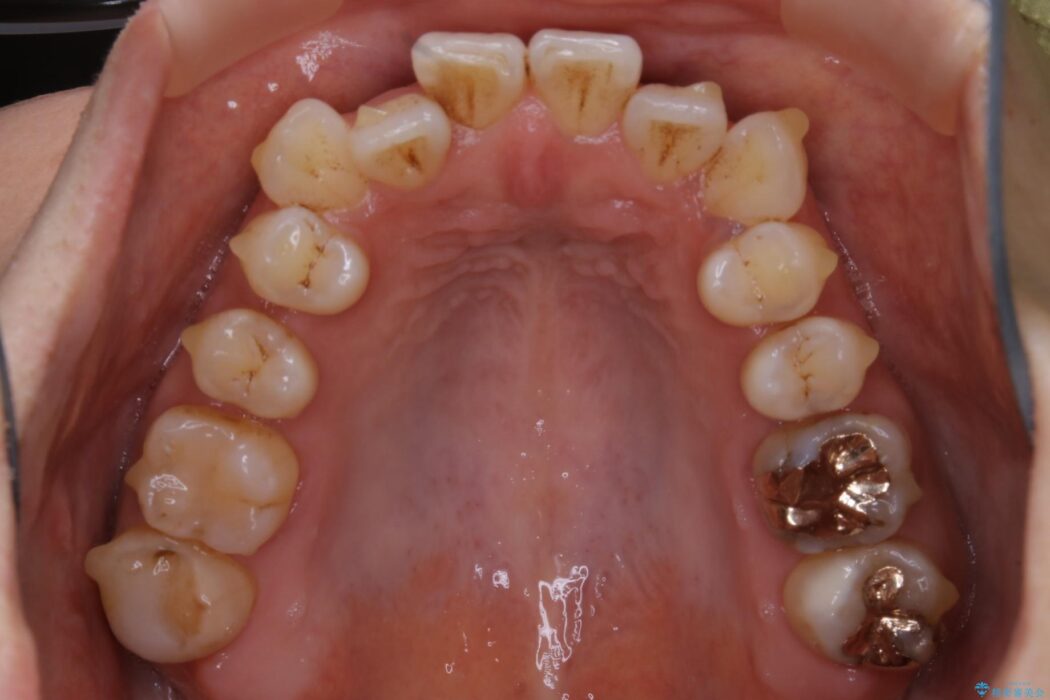

【20代女性】開咬の隙間と歯列の凸凹をまとめて改善する

開咬により上下の噛み合わせが悪く、歯列の凸凹も合わせて治療したいとのことで来院されました。

なるべく非抜歯にて治療をするためインビザライン(マウスピース)とマイクロインプラントを併用した治療を行いました。

マウスピースとマイクロインプラントの併用により矯正するための隙間を確保し、治療期間は長くなりますが非抜歯できれいな歯列弓を得ることができます。